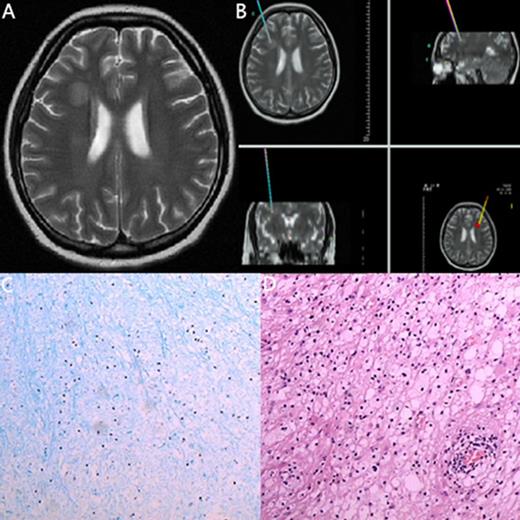

| 14 | 23/F | ALL (B cell) | 23/1 mo after allo-ASCT | headache | MRI: The right paracele white matter lesions visible long T1, long T2 signal, the boundary is not clear, edema is not obvious, no enhancemen. | Degenerative disease | Nerve cell degeneration | Improved |